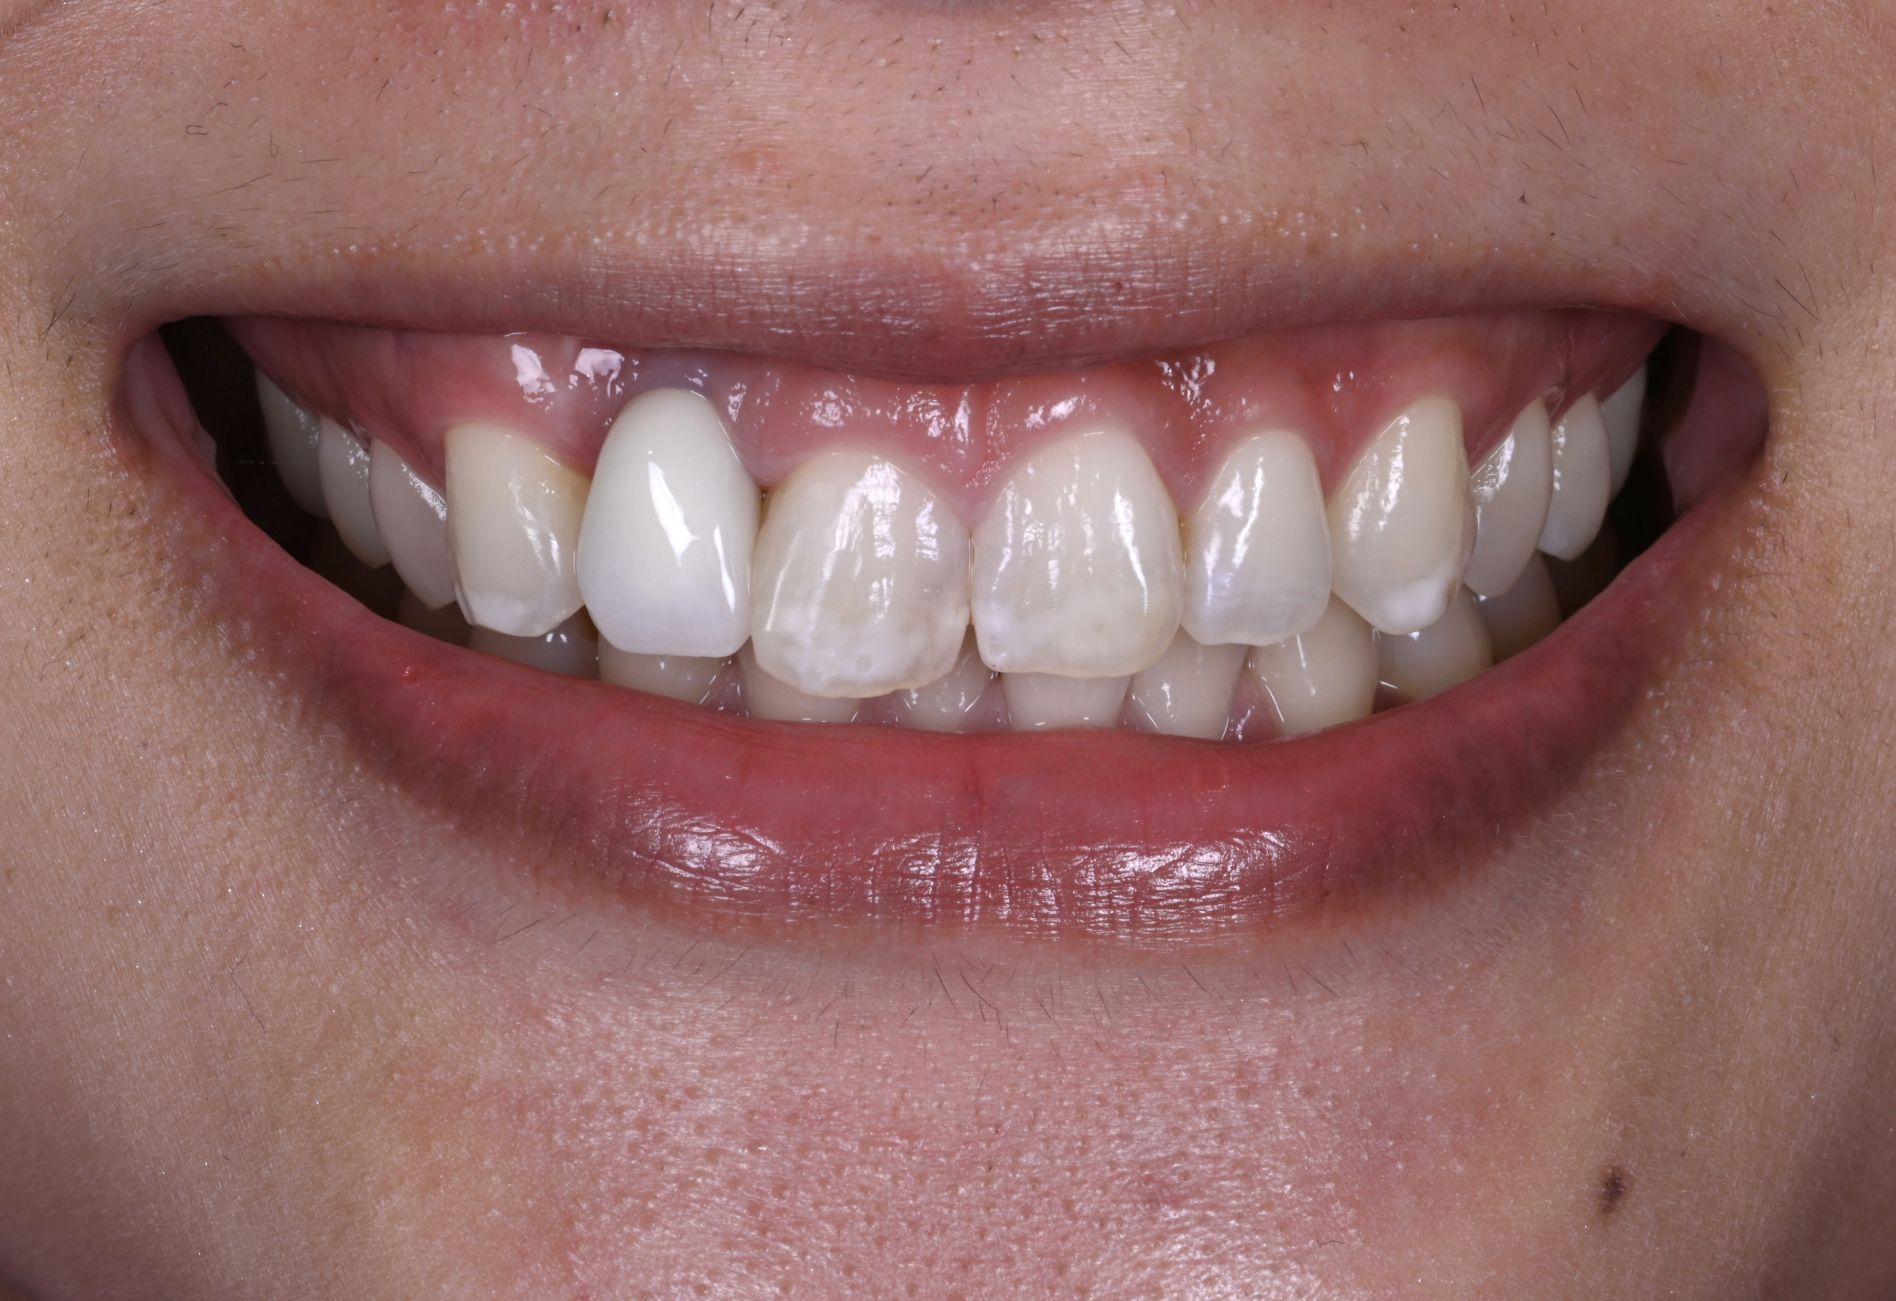

骨造成・歯肉移植を伴うインプラントのやり直し症例

Before

After

年代

40歳代

主訴

前歯5本をやりかえたい。

背景

小学生の頃に転んで前歯を折ってしまってずっと前歯で苦労してきた。

治療

旧インプラント撤去・骨造成・歯肉移植・インプラント治療・セラミック治療

治療期間

1年6ヶ月

治療費用

1,870,000円(税込)